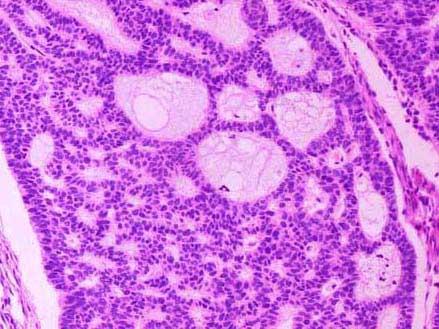

问题 如图均为恶性肿瘤,图1来源于鳞状上皮,图2来源于基底细胞,图3来源于脂肪细胞,图4来源于滑膜,以下依次命名正确的是 ( )

选项 A.鳞状细胞癌、基底细胞瘤、脂肪肉瘤、滑膜瘤 B.鳞状细胞癌、基底细胞瘤、脂肪肉瘤、滑膜肉瘤 C.鳞状细胞癌、基底细胞癌、脂肪肉瘤、滑膜肉瘤 D.鳞状细胞癌、基底细胞肉瘤、脂肪肉瘤、滑膜瘤 E.鳞状细胞癌、基底细胞瘤、脂肪瘤、滑膜肉瘤

答案 C